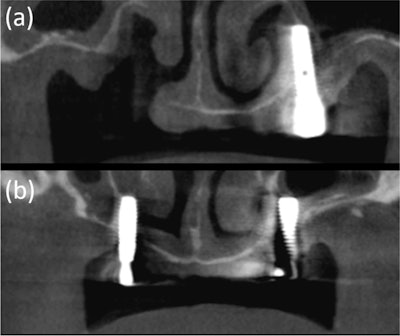

The 64-year-old's CBCT images showed a discontinuity of the inferolateral cortex of the nasal cavity and oronasal fistula, which is observed as a tissue defect on the x-ray. (a) Moreover, the residual implants on both sides perforated the nasal cavity and are placed just medial to the maxillary sinus.

The x-ray and CT images of a 76-year-old woman. On the x-ray, white arrows indicate the hard palate line, while yellow arrows indicate the antral floor. Images of the implants in the left premolar and molar areas are superimposed above the hard palatal line. (b-c) The CT images revealed nasal floor perforation by an implant of the maxillary left premolar.

The woman had pain in the mandibular right posterior region and was diagnosed with osteomyelitis of the right posterior mandible based on clinical and imaging exams. CT images showed her dental implants had perforated the nasal floor of the maxillary left premolar.

However, panoramic x-rays revealed that the implants of the left maxillary premolar region were placed normally between the lateral wall of the nasal cavity and the faint medial wall of the maxillary sinus, the authors of the case study wrote.